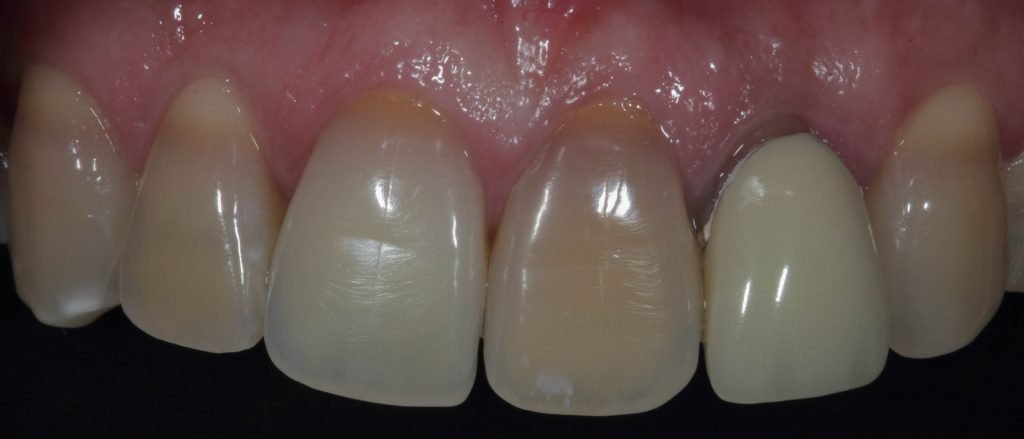

Punto Bajío Casos Clínicos Prótesis Fija sobre Implante unitario Inicio Provisional Final Prótesis Parcial Fija sobre 2 Implantes 2 Implantes Final Prótesis Bucal Removible Inicial Inicial Superior Inicial Inferior Rayos X Inicial Rayos X Inicial Frontal Final Final Superior Final Inferior Prótesis Parcial Fija/ Coronas de Circonio Sonrisa Inicial Foto Inicial Foto Inicial Inferior Foto Final Inferior Foto Final Sonrisa Final Prótesis Total Protesis Inmediatas 1 Protesis Inmediatas 2 Prótesis Removible/ Coronas Metal-Ceramica Carillas Incrustaciones Endodoncia